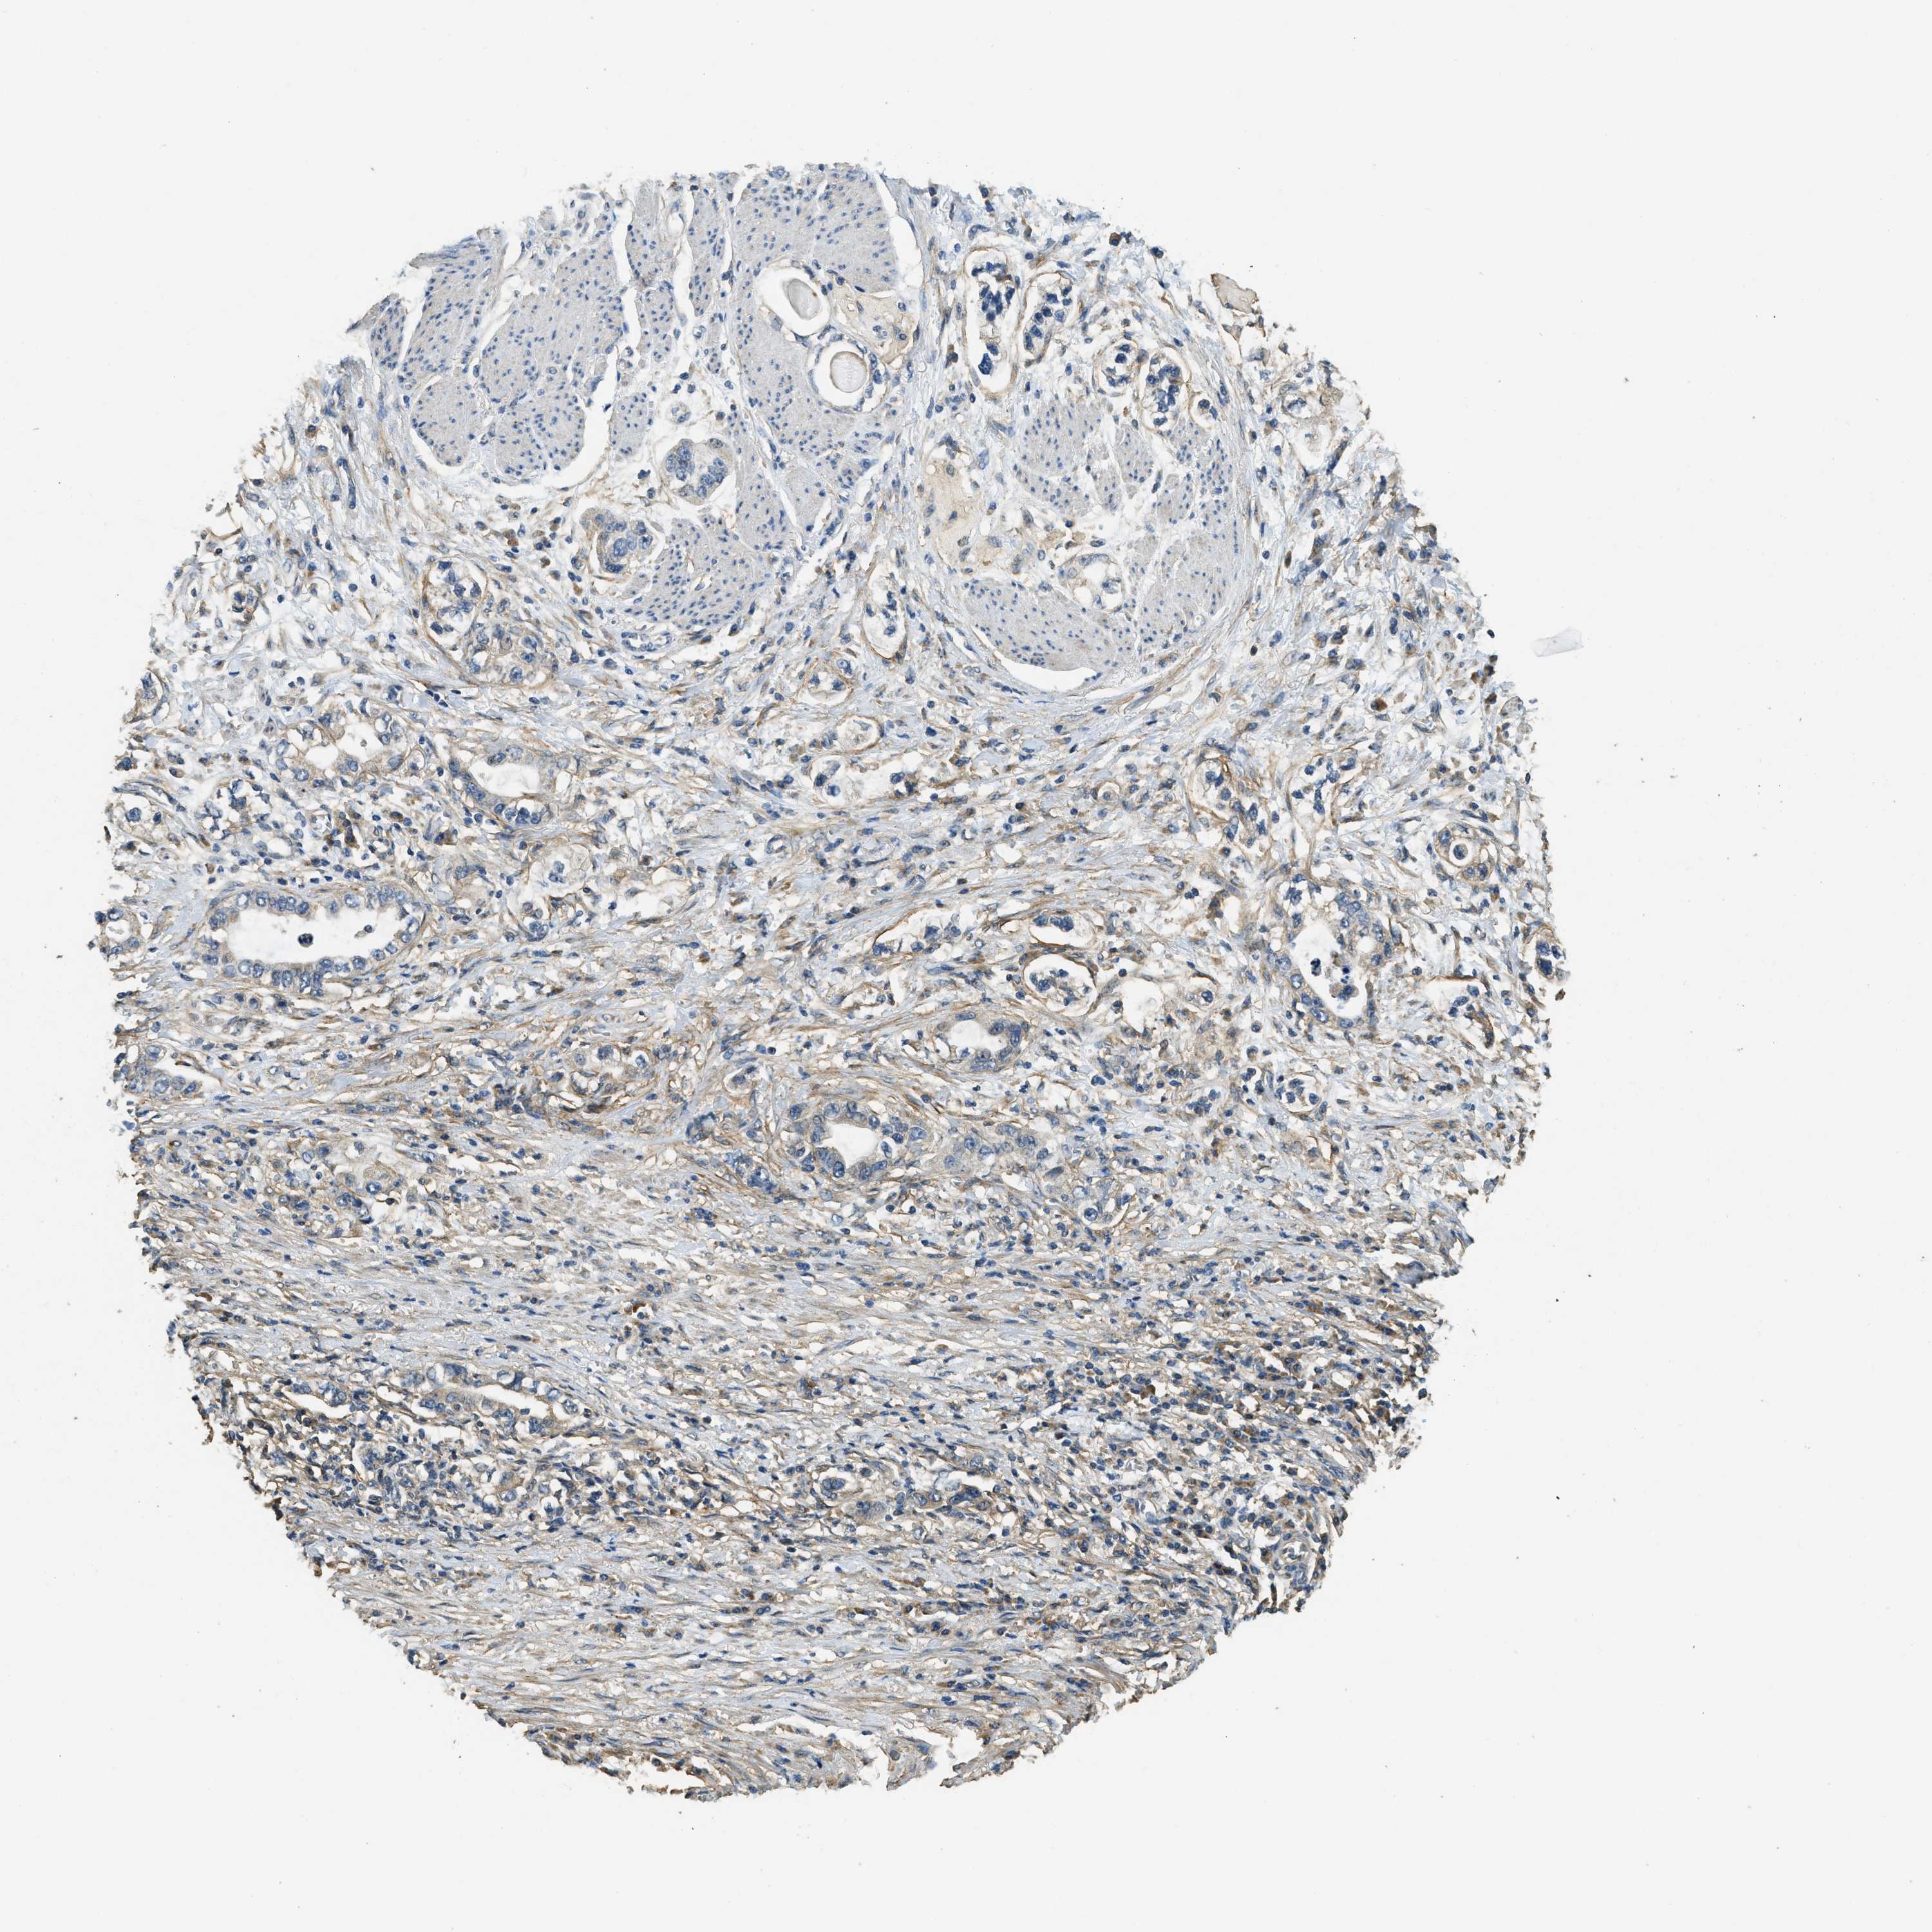

STOMACH CANCER - Protein expressioni

A mouse-over function shows sample information and annotation data. Click on an image to view it in a full screen mode. Samples can be filtered based on level of antibody staining by selecting one or several of the following categories: high, medium, low and not detected. The assay and annotation is described here.

Antibody stainingi

Antibody staining in the annotated cell types in the current human tissue is reported as not detected, low, medium, or high, based on conventional immunohistochemistry profiling in selected tissues. This score is based on the combination of the staining intensity and fraction of stained cells.

Each image is clickable and will lead to virtual microscopy that enables deeper exploration of all samples and also displays staining intensity scores, fraction scores and subcellular localization as well as patient and tissue information for each sample.

Antibody HPA009285

Antibody HPA017139

Antibody CAB017826

Staining

High

Medium

Low

Not detected

Intensity

Strong

Moderate

Weak

Negative

Quantity

>75%

75%-25%

<25%

None

Location

Nuclear

Cytoplasmic/membranous

Cytoplasmic/membranous,nuclear

Adenocarcinoma, NOS

Adenocarcinoma, High grade